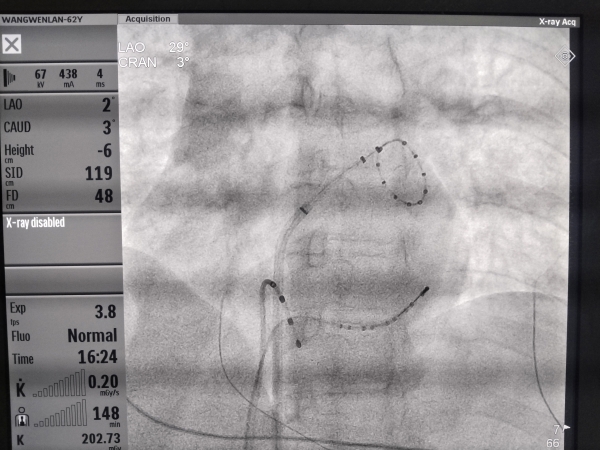

5月25日,乌苏市人民医院心血管内科团队在上级医院专家指导下,为62岁的王红成功实施塔城地区首例射频消融微创手术,这一手术的成功开展,标志着塔城地区心律失常治疗正式迈入精准介入新时代。

手术当日,心血管内科团队在三维电生理标测系统引导下,通过患者股静脉将导管送至心脏。借助射频能量,医生精准消融肺静脉口异常放电的病灶,从根本上阻断房颤触发机制。整台手术历时约2小时,患者全程保持清醒,术后6小时便下床活动。